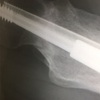

O先生「止まりましたね。ズレてしまったと思ったんですが、ここで止まりました。このまま止まってくれたら、大丈夫な気がします。」

M「先生、そもそも…前のレントゲンではズレたように見えたんですが、今回ではズレが戻っているように見えます。これ、前回のレントゲンでズレたように見えたのは写り方の問題だったのではないですか」

O先生「そうかもしれませんね。毎回同じ姿勢で撮るように技師さんにはお願いしていますが、全く同じ姿勢で取れるわけではないので、その都度レントゲンの写り方が変わってしまう事はありえる。僕は前のレントゲンを見た時は、これは厳しいなと思ったんですが、なんかいける気がしてきましたね。多分大丈夫なんじゃないかな」

5週間後の2017年12月に病院に行きました。部屋に入るなり、先生はマウスをカチカチして興奮しながら早口で言いました。

「これ見てください!完全にくっついてる。これはついたと思います。折れたところが埋まったでしょ。これは勝ったな、これは勝ったぞ」

こんなに興奮した様子の先生は初めて見ました。体重をかけた事で骨に刺激が加わり、骨癒合が促進されたようです。やはり骨には体重をかけないと治る力が戻ってきません。だから体重をかけたくて仕方がなかった。しかし、あまり早期に体重をかけてしまうとズレてしまう。4ヶ月もの免荷に耐えられなくなり、セカンドオピニオンをもらおうか、勝手に荷重開始しやうかと悩んだこともありました。